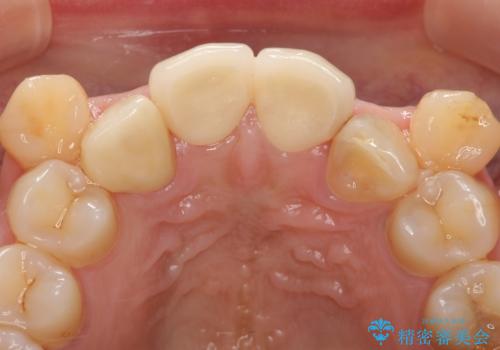

その後右上1,2番目及び左上1番目の歯に対してオールセラミッククラウンによる補綴を行いました。

今回用いたオールセラミッククラウンはジルコニアフレームという白い素材の上にセラミックを盛っているため、審美性が非常に高いのが特徴です。

また、ジルコニアは人工ダイヤモンドの材料にも使われているほど高い強度を持っており、そのためオールセラミッククラウンは審美性だけでなく、奥歯やブリッジの補綴も可能とするクラウンです。